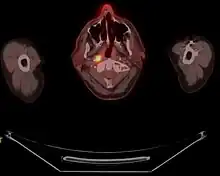

Carcinome du nasopharynx

Diagnostic

La biopsie fait le diagnostic. Une évaluation de l'extension est indispensable permettant une prise en charge optimale[7],[8].